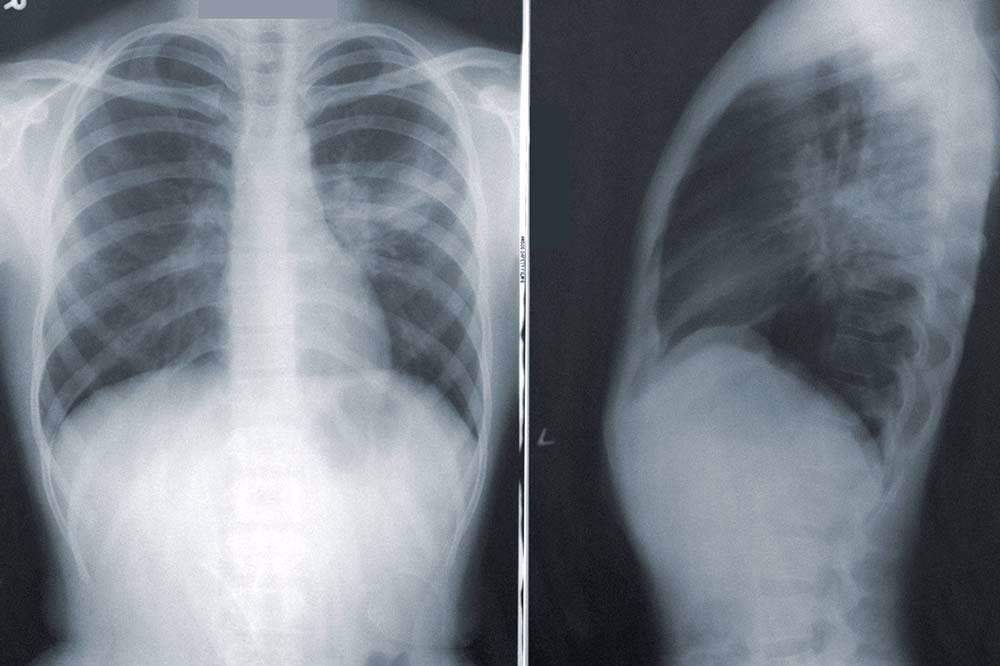

Når det kommer til CAP, er billeddiagnostik afgørende. Et røntgenbillede af thorax er normalt det første skridt: det er hurtigt, tilgængeligt og nyttigt til at opdage infiltrater, konsolideringer eller pleurale effusioner. Men det har sine begrænsninger – især i de tidlige stadier af sygdommen eller hos patienter med f.eks. KOL, hvor lungebilledet i forvejen kan være forandret.

Når det kliniske billede er uklart eller mere komplekst, bliver en CT-scanning et værdifuldt værktøj. Med større nøjagtighed hjælper den med at differentiere lungebetændelse fra andre lungesygdomme, såsom lungeemboli eller atelektase. Ulempen? Radiologiske rapporter kommer ikke altid hurtigt tilbage, hvilket kan forsinke opstarten af behandlingen.